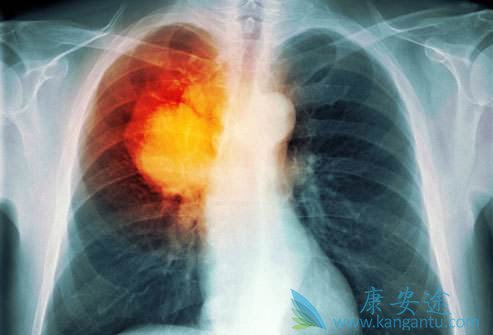

肺癌脑转移分为脑实质转移和脑膜转移

脑转移分为脑实质转移和脑膜转移。实质转移最常见部位为大脑半球,随后依次为小脑、脑干。脑膜转移少见,预后更差。肺癌脑转移发生率较其他恶性肿瘤高,约20-65%的患者会在病程中出现。SEER数据称,非转移性腺癌、鳞癌、大细胞癌脑转移发生风险分别为11%、6%、12%。小细胞肺癌首诊时发病率即为10%,存活2年以上患者发生率达60-80%。

肺癌脑转移